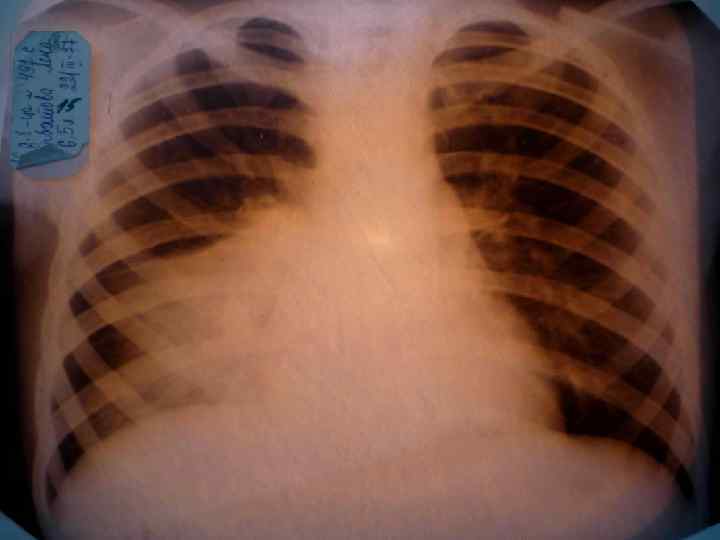

Долевая пневмония характеризуется лобарным пневмоническим инфильтратом. Крупозная ( пневмококковая) пневмония диагностируется прежде всего по клиническим данным. Крупозная пневмония сохраняет свою типичную картину пневмококковой пневмонии: острое начало с характерными клиническими данными, циклическое течение, несклонность к деструкции, гомогенной и лобарной инфильтративной тенью при рентгенологическом исследовании. Вместе с тем, широкое использование антибиотиков способствовало значительному снижению числа крупозных пневмоний у детей. Интерстициальная – редкая форма пневмоний, при которой оказывается поражен прежде всего интерстиций. Как правило, интерстициальная пневмония обусловлена вирусами, пневмоцистами, внутриклеточными микроорганизмами и грибами.

Морфологическую форму пневмонии определяют по клинико – рентгенологическим данным: выделяют очаговую, очагово – сливную, долевую ( крупозную), сегментарную и интерстициальную пневмонии. Очаговая – наиболее распространенная форма. Пневмонические очаги чаще бывают размером 1 см и более. Очагово – сливная – инфильтративные изменения в нескольких сегментах или во всей доле легкого, на фоне которых могут быть видны более плотные участки инфильтрации и/или полости деструкции. Сегментарная – в процесс вовлекается весь сегмент, который, как правило, находится в состоянии гиповентиляции, ателектаза. Морфологическая картина воспаления при очаговых и сегментарных пневмониях связана с первичным инфекционным воспалением в бронхах, что дает основание отнести эти варианты поражения легочной ткани к бронхопневмониям, нередко сопровождающихся бронхообструктивным или бронхообтурационным синдромами. В настоящее время данный тип пневмоний у детей встречается наиболее часто.